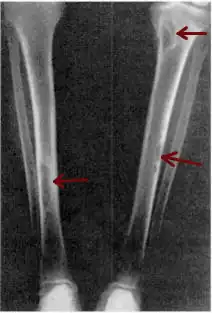

| Osteitis fibrosa cystica of the tibia. Arrows point to the brown tumors which are typically present in bones of people with OFC. | |

X-rays may also be used to diagnose the disease. Usually, these X-rays will show extremely thin bones, which are often bowed or fractured. However, such symptoms are also associated with other bone diseases, such as osteopenia or osteoporosis.[29] Generally, the first bones to show symptoms via X-ray are the fingers.[22] Furthermore, brown tumors, especially when manifested on facial bones, can be misdiagnosed as cancerous.[29] Radiographs distinctly show bone resorption and X-rays of the skull may depict an image often described as "ground glass" or "salt and pepper".[30][31] Dental X-rays may also be abnormal.[2]

Cysts may be lined by osteoclasts and sometimes blood pigments, which lend to the notion of "brown tumors." Such cysts can be identified with nuclear imaging combined with specific tracers, such as sestamibi.[3] Identification of muscular degeneration or lack of reflex can occur through clinical testing of deep tendon reflexes, or via photomotogram (an achilles tendon reflex test).[24][32]